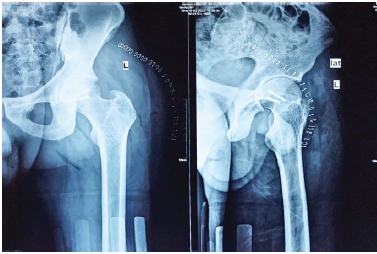

Giant Cell Tumor of the Proximal Femur with Pathological Fracture of Femoral neck

Gagandeep Gupta , Abhishek Singh , Shivang Kala , Akhilesh Saini , Shristi Singh , Sopan Shende

………………………………p.113-118